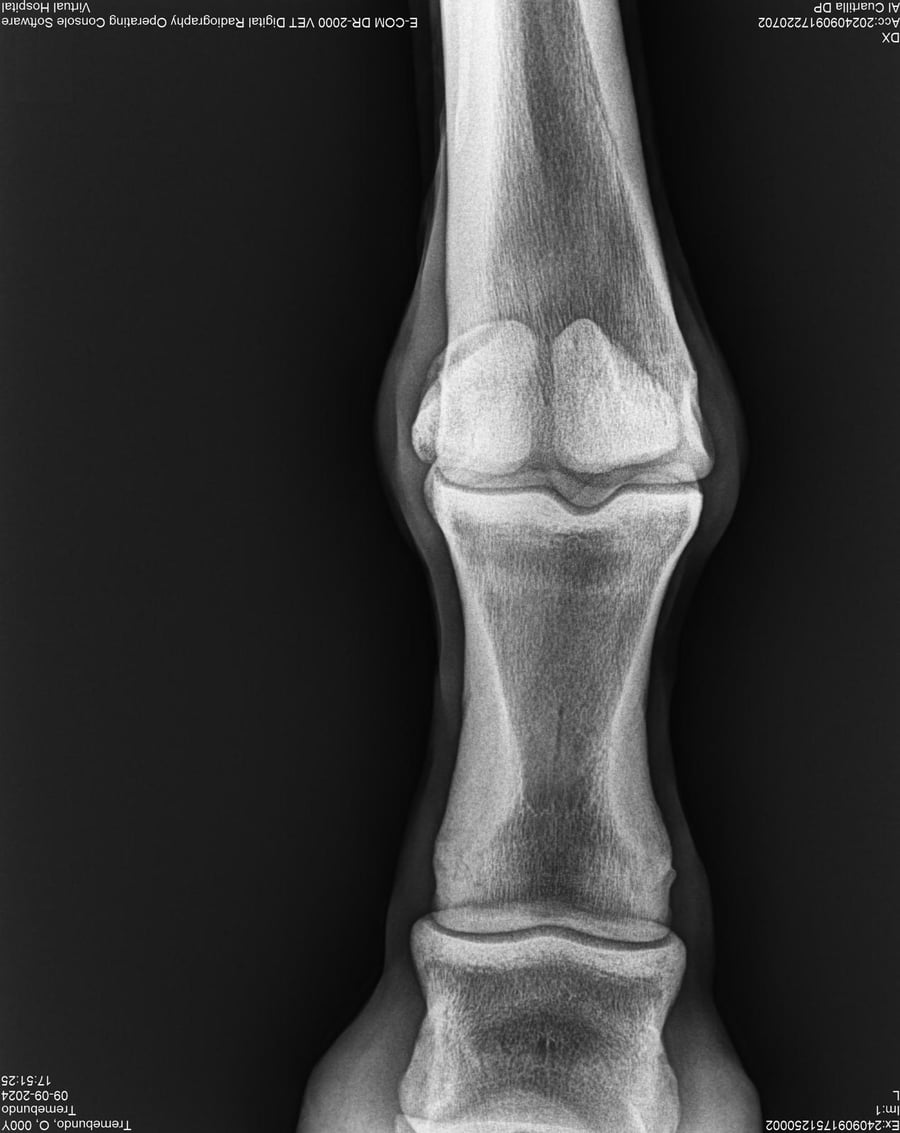

LOTE 37, TREMEBUNDO

Generacion 2022